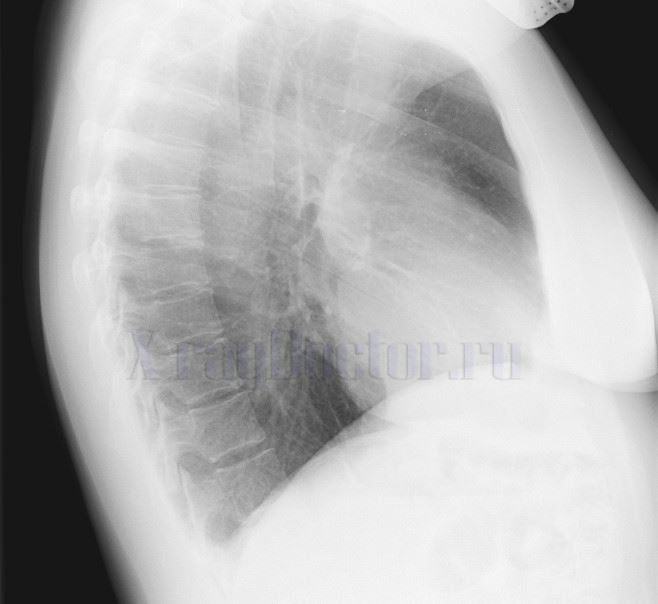

Снимки осуществляются в прямой и боковой проекциях. При необходимости исследование можно дополнить косой рентгенограммой.

Тяжелые бронхиты требуют двустороннего исследования. С этой целью рентген лучше проводить через 5 дней поочередно для одного и второго легкого.